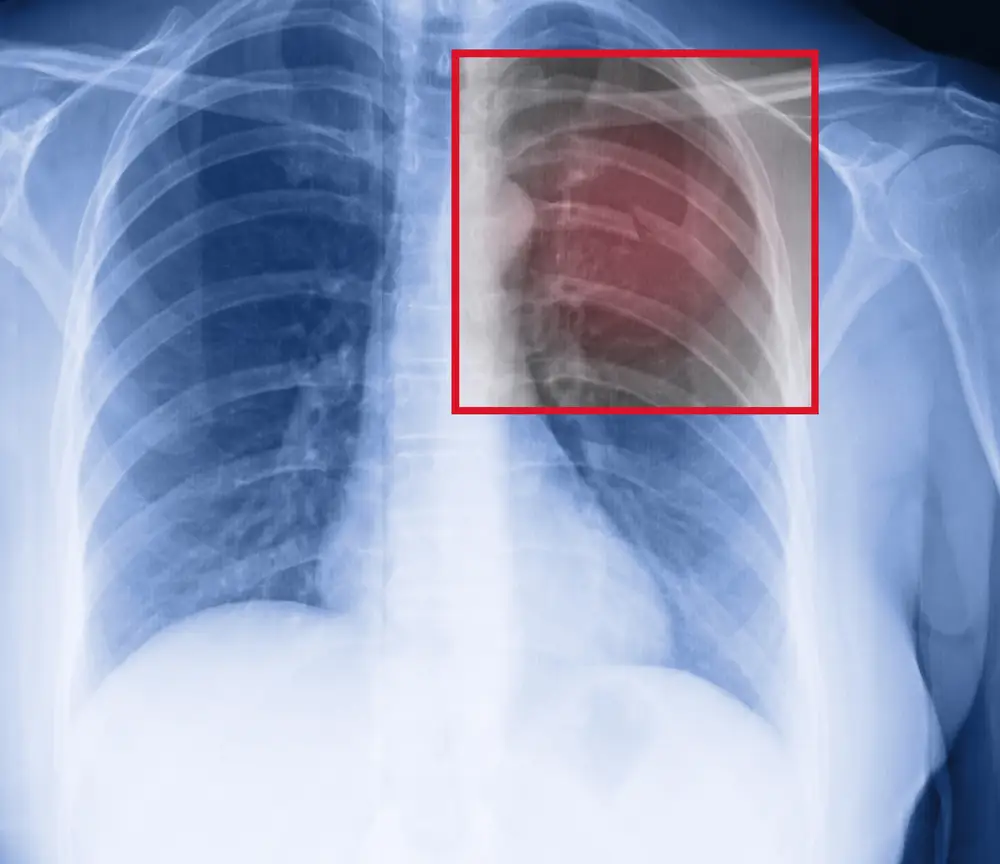

Rib Fracture Stock Photos & Rib Fracture Stock Images Alamy Does Heat Help A Broken Rib Broken ribs involve fractures of the bones of. — it takes time for hard bone to replace soft bone and heal the fracture. — most broken ribs heal on their own within six weeks. — bruised ribs involve muscles, cartilage, tendons, fascia, and other soft tissues surrounding the ribcage. Ice the area for 20. Being less active. Does Heat Help A Broken Rib.